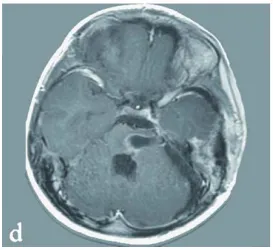

术后患儿神经症状持续改善。术后10天MRI检查证实海绵状血管瘤完全切除,显示先前严重增大的脑干已获减压(图1 d)。患儿出院后接受进一步神经功能康复治疗。

图d 术后:显示海绵状血管瘤完全切除,第四脑室大小恢复,脑干压迫解除。